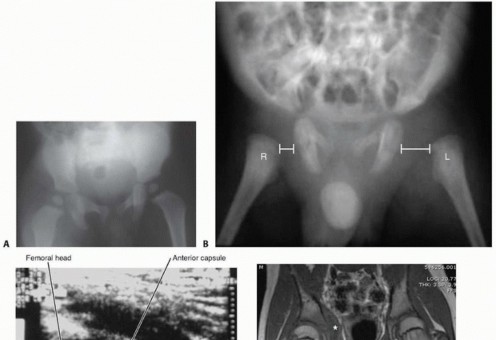

Plain radiographs (

FIG 3A

)

Key features include hip abduction, increased soft tissue density, widened medial joint space, osteopenia if the infection is long-standing, and femoral or acetabular osteolytic lesions.

A particularly worrisome finding in the neonate is a painful dislocated hip (

FIG 3B

). Bone lesions and destruction are typically delayed 1 to 2 weeks.

Ultrasound imaging (

FIG 3C

) is performed bilaterally, with images obtained along the axis of the anterior femoral neck. This is very specific for detecting intra-articular fluid in the hip.

Because the pelvis is deep and difficult to examine, magnetic resonance imaging (MRI) is an extremely useful imaging modality to examine the tissues surrounding the hip joint or within the pelvis (

FIG 3D-F

).

It is the preferred imaging technique if the hip joint moves better than would be expected for septic hip arthritis but the patient has symptoms within or near the pelvis suggesting myositis or an abscess.7, 13

MRI is useful if by 48 hours there is an inadequate response to treatment of septic hip arthritis, suggesting persistent hip joint infection, pelvic osteomyelitis, or infection in the muscles near the hip joint.

With the changing clinical spectrum of musculoskeletal infections, the severity of infections is increasing. MRI is becoming the preferred imaging modality to provide detailed anatomy, clinical classification, and

clarify early surgical decision making.5

FIG 3

• Diagnostic imaging.

A,B.

Anteroposterior (AP) radiographs.

A.

The right hip is held in abduction with increased soft tissue density and slight lateral displacement of the femoral head.

B.

Left hip of an infant showing acute displacement from septic hip arthritis. The left proximal femur is laterally displaced compared with the right.

C.

Ultrasound imaging of hip along axis of the femoral neck. The distance between the femoral neck and head is shown by the

red line

. There is increased intracapsular fluid.

D-F.

MRIs in an 11-year-old boy with fever and pain with internal rotation of the hip. He was limping but able to walk. ESR was 50 mm per hour and CRP level was 5.8 mg/L. The radiograph was normal.

D.

T1-weighted coronal image of pelvis. There is an abscess (

asterisk

) within the obturator internus muscle.

E.

T2-weighted coronal image of pelvis. The abscess (

) is more apparent, as is the involvement of the acetabulum (

solid dot

) and small hip joint effusion (

dashed outline